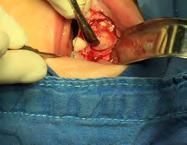

Se llevó a cabo la intervención quirúrgica bajo anestesia general con una intubación nasotraqueal (protocolo completo que se maneja en la Unidad de Especialidades Odontológicas. SEDENA), se procedió al acto quirúrgico siguiendo los protocolos, antisepsia del campo y colocación de compresas según técnicas, se inició, previa anestesia local con lidocaína al 2% con epinefrina 1:100,000 diseñando un colgajo de Newman parcial para levantar un colgajo mucoperiostico de espesor total de tipo axial mucoperiostico (Figura 4A)

Se realizó la osteotomía, después de exponer la masa tumoral con instrumental de rotación de alta velocidad con fresa 702 con abundante irrigación, se seccionó la masa tumoral y con el objetivo de no lesionar estructuras anatómicas vecinas y en relación con la lesión, se levantó la cortical ósea con legra y se accede a la lesión, de forma controlada y progresiva (Figura 4B).

Figura 4. A-E. Secuencia técnica quirúrgica.

Se realizó la escisión completa de la masa tumoral, mediante curetaje; se extrajo el órgano dentario 63, y se enucleo el tumor, el cual fue enviado a estudio histopatológico, los múltiples dentículos fueron extraídos hasta limpiar el lecho quir ú rgico por completo, se alisaron aristas de hueso con pieza de mano de alta velocidad y lima para hueso, se lavó con suero fisiológico y se procedió a suturar (Figura 4C-4E).